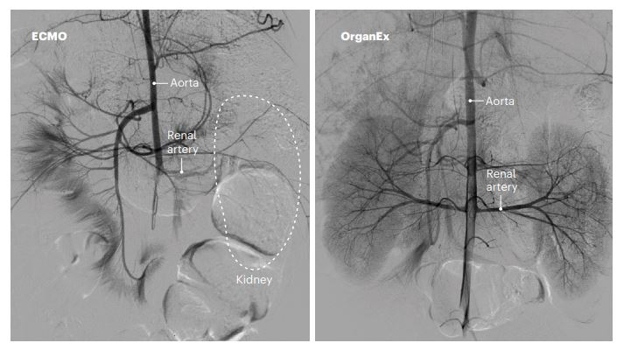

22. El journal @PublishInNature publicó la experiencia con el #Organex, un sistema de perfusión pulsátil extracorpórea y perfusión citoprotectora, que después de 1 hora de isquemia caliente, regresó a los órganos de varios cerdos, a sus procesos moleculares y celulares normales.